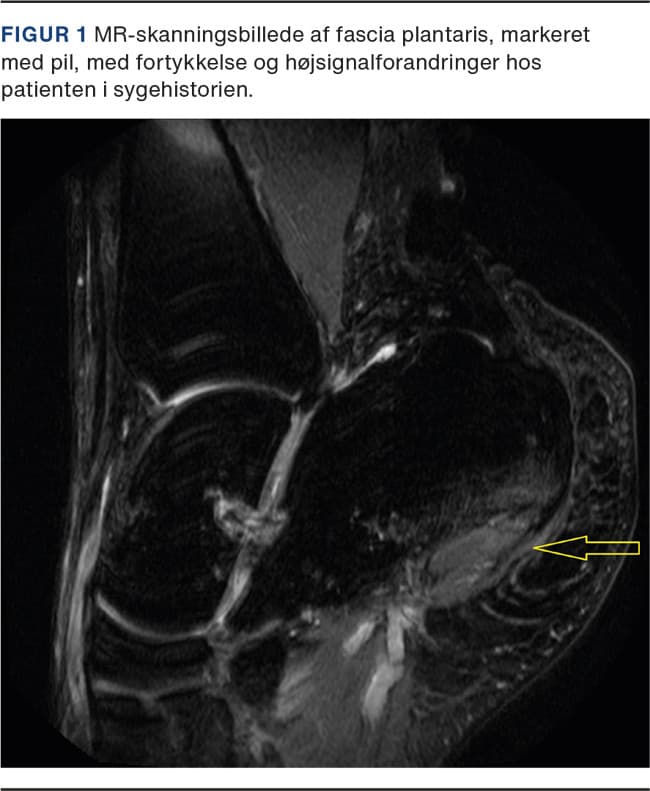

Under udredning blev der udført UL-skanning af fødderne, der viste udtalt, bilateral fasciitis plantaris med betydelig Doppler-aktivitet som tegn på inflammation. Efterfølgende MR-skanning af fødderne viste ligeledes markante forandringer af fascia plantaris (Figur 1) ved tilhæftningen på calcaneus og samtidig knoglemarvsødem ved tuber calcanei. Klinisk og paraklinisk var der ikke holdepunkter for sarkoidose, da PET/CT- og lungefunktionsundersøgelser var normale. Patienten havde ikke hududslæt, artritis eller inflammatoriske rygsmerter og var humant leukocytantigen (HLA)-B27-negativ. Mistanke om underliggende psoriasisartritis eller ankyloserende spondylitis som årsag til symptomerne blev således afkræftet. Patienten ønskede ikke binyrebarkhormoninjektion, så der blev i stedet behandlet med peroralt givet prednisolon. Dette, kombineret med fysioterapeutisk instruks mht. udspændingsøvelser samt indlægssåler, gav reduktion af symptomerne.